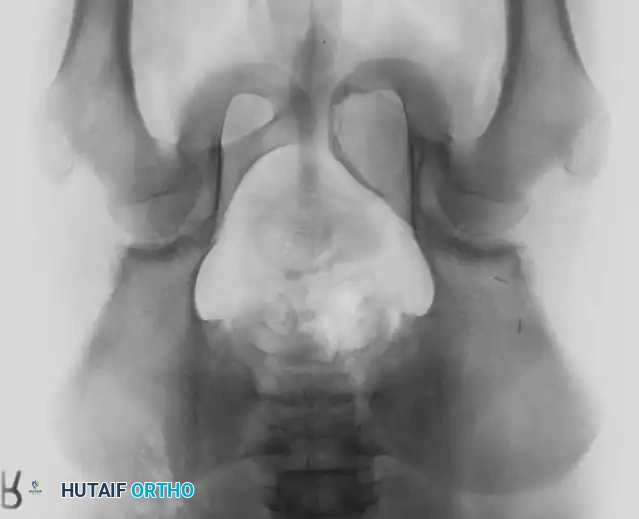

Fig. 20-22: (A and B) Pathological fracture of the right proximal tibia occurring through a large, expansile “brown tumor” of hyperparathyroidism in a 55-year-old woman.